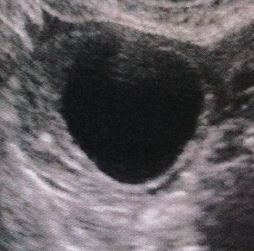

Я двести раз переспросила, может это ЖТ? А она НЕТ 100%. К слову, у этого узиста была в первый раз. График, фото ЛЯ:

Я так понимаю когда полость не полностью черная а частично серое, как у меня на фотке сверху, то это не фоликул. Я еще на мониторе присматривалась к нему и в некоторых проекциях этой серой массы было оч много. Сейчас попробую вам ссылку найти ту с примерами